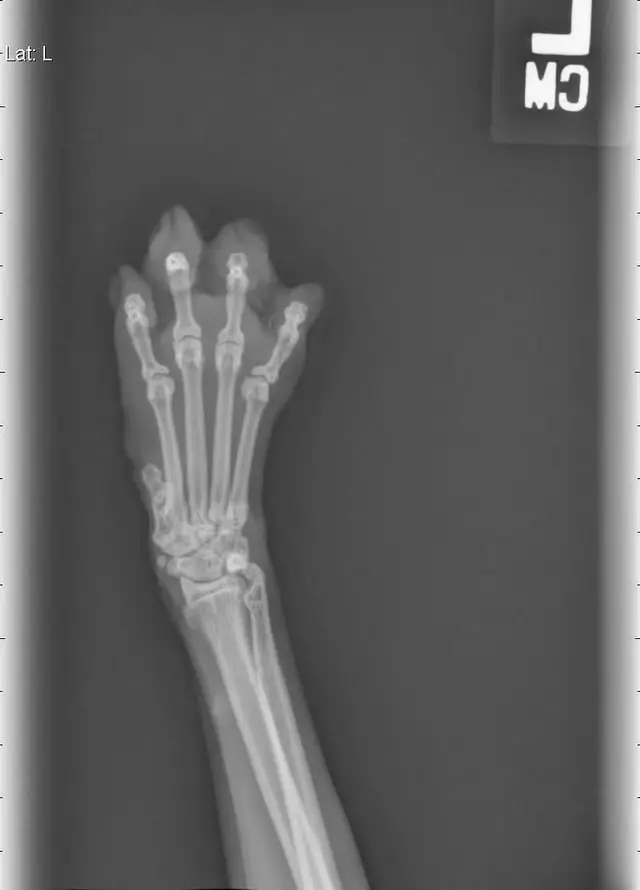

i mean. this is a completely normal pediatric knee x-ray: